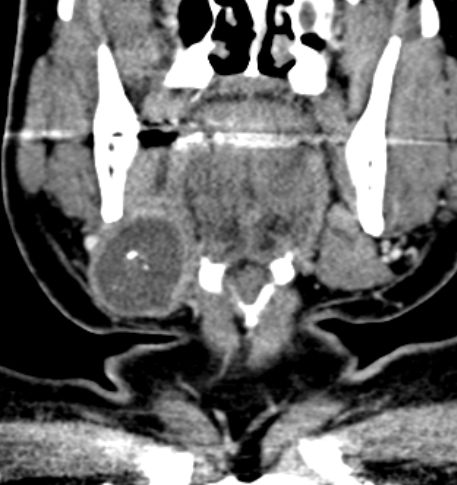

55-jähriger Mann mit einem Karzinom der linken G. submandibularis pT3 pNo Mo![]() |